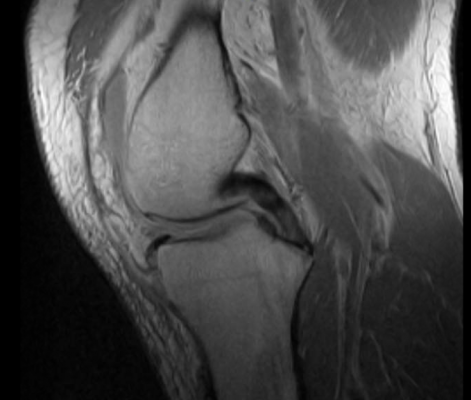

January 11, 2018 – Obese people who lose a substantial amount of weight can significantly slow down the degeneration of their knee cartilage, but only if they lose weight through diet and exercise or diet alone, according to a new magnetic resonance imaging (MRI) study presented at the annual meeting of the Radiological Society of North America (RSNA), Nov. 26-Dec. 1 in Chicago.

The researchers studied 760 men and women with a body mass index of greater than 25 from the Osteoarthritis Initiative, a nationwide research study focused on the prevention and treatment of knee osteoarthritis. The patients either had mild to moderate osteoarthritis or risk factors for the disease. Patients were divided into a group of 380 patients who lost weight, and a control group of 380 patients who lost no weight. The weight-loss group was further segmented by weight loss method: diet and exercise, diet alone and exercise alone. The researchers used MRI to quantify knee osteoarthritis at the beginning of the study, at 48 months and at 96 months.